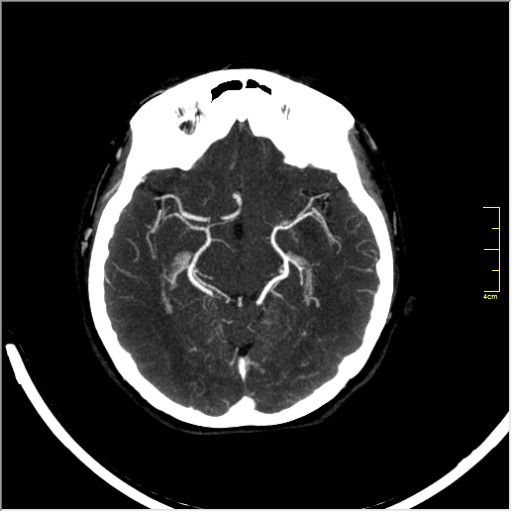

КТ ангиография головного мозга

Стандартная процедура в современной работе КТ кабинета, весьма несложна в исполнении.

Сканы представленны в режиме MIP.